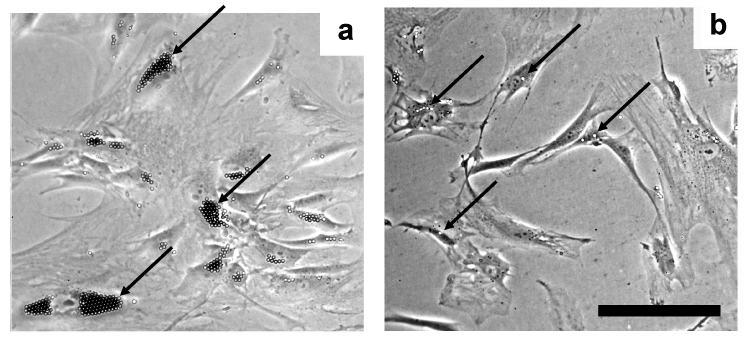

| Figure 1: Primary culture of human microvascular endothelial cells (HMEC). A representative colony of microvascular endothelial cells associated with anti-CD31 beads 24h after isolation (a), and after the fi rst passage (b). There were no cells not associated with CD31 beads that would represent contaminating cells. Images were obtained using an inverted phase contrast microscope (scale bar: 50 µm). Arrows show beads attached to cells. |